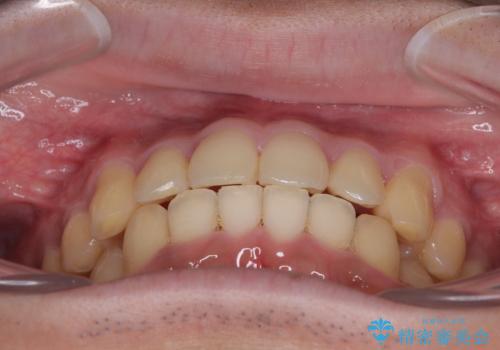

- 上下前歯の捻れやデコボコを気にして来院された患者様です。

マウスピース矯正でもワイヤー矯正でも対応可能でしたが、極力楽をして治したいとのことでワイヤー装置にて治療をおこなうこととしました。

口元はそれほど突出しておらず、患者様自身も気にしていらっしゃいませんでしたが、前歯の捻れやデコボコを解消すると、前方に拡大され、治療後に出っ歯仕上がりとなるリスクがあったため、補助装置により上顎臼歯を後方移動していくこととしました。

昼休みを活用して通院してくださり、1年半であっという間に終えることができました。